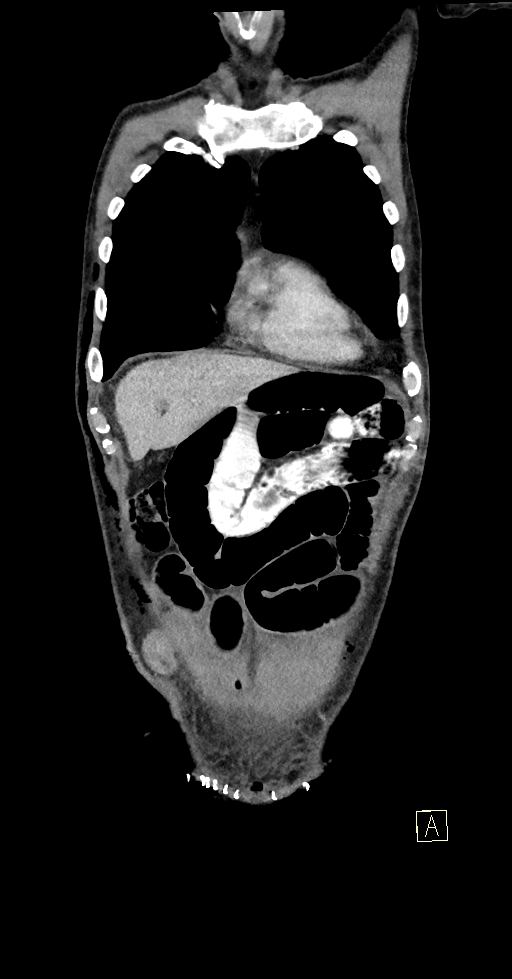

Figura 3: coronal venos din achiziție CT torace, abdomen și pelvis

Discuţie caz nr 124: Pacient postoperator precoce pentru tumoră rectala prezintă simptome de ocluzie intestinală. Examinarea CT evidențiază creștere de calibru a anselor intestinale proximale ce conțin nivele hidro-aerice cu decalibrare la nivelul liniei antero-laterale de partea dreaptă unde evoluează o ansa de intestin subțire. Deasemenea, pacientul prezintă o hernie inghinală stânga fără ca aceasta sa fie cauză de ocluzie, precum și modificări postoperator precoce la nivelul peretelui anterior abdomino-pelvin.